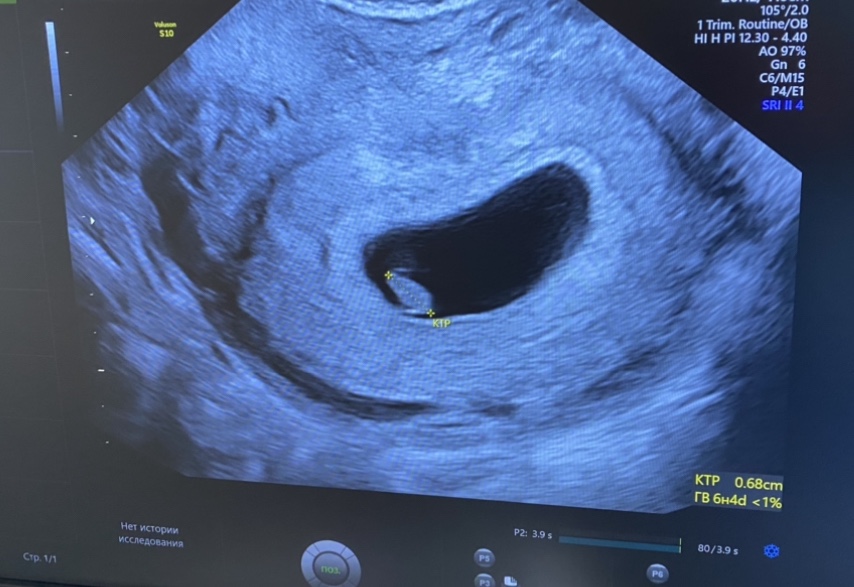

Ну всё 🥰 побывали на узи))) всё хорошо, сердечко послушала ❤️ такая кроха 🥹

рубец хороший🤞🏻 это самое главное, а то переживала